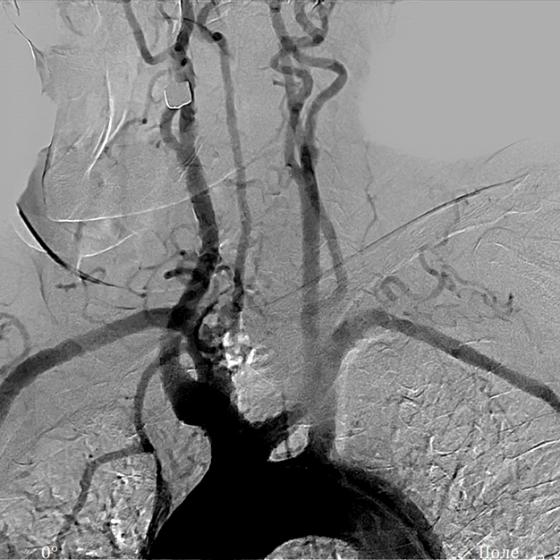

Высокое качество изображения на мобильных рентгенохирургических аппаратах СРТ достигается за счет цифровой системы визуализации, которая позволяет видеть даже самые мелкие дефекты и патологии. Модель «СРТ» с плоскопанельным детектором обеспечивает визуализацию даже сосудов. Режимы импульсной рентгеноскопии, рентгеноскопии с пониженной дозой и рентгеноскопии повышенного качества в сочетании с широким набором программ органоавтоматики, которые учитывают возраст и комплекцию пациента, позволяют получать качественное изображение при минимальной дозовой нагрузке.

Благодаря эффективной системе охлаждения излучателя обеспечивается высокая длительность рентгеновского контроля, обусловливающая использование аппарата для широкого спектра диагностических и лечебных хирургических манипуляций на сердце и сосудах. Режим субтракционной ангиографии, сосудистый пакет, маршрутизация и возможность выбора маски создают необходимые условия для успешного применения аппарата в коронарографии, ангиографии и при контроле электрофизиологических процедур.